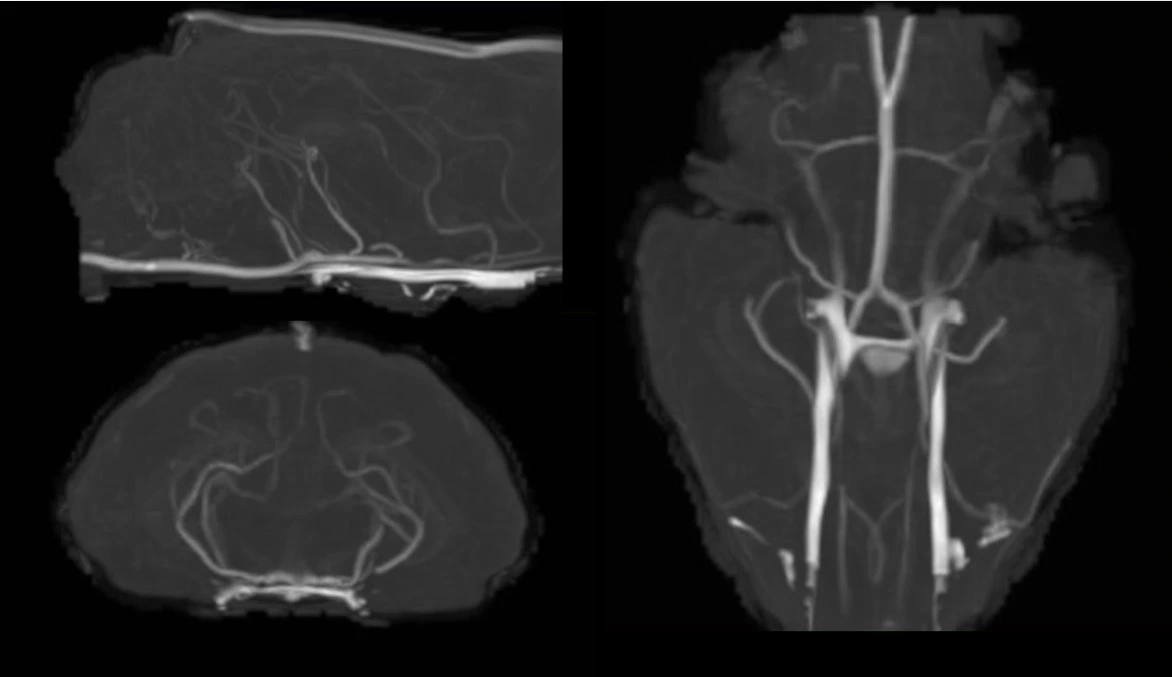

In-vivo Time-of-Flight MRI Angiography in the ferret brain. (Laurel Dieckhaus)

Laurel Dieckhaus